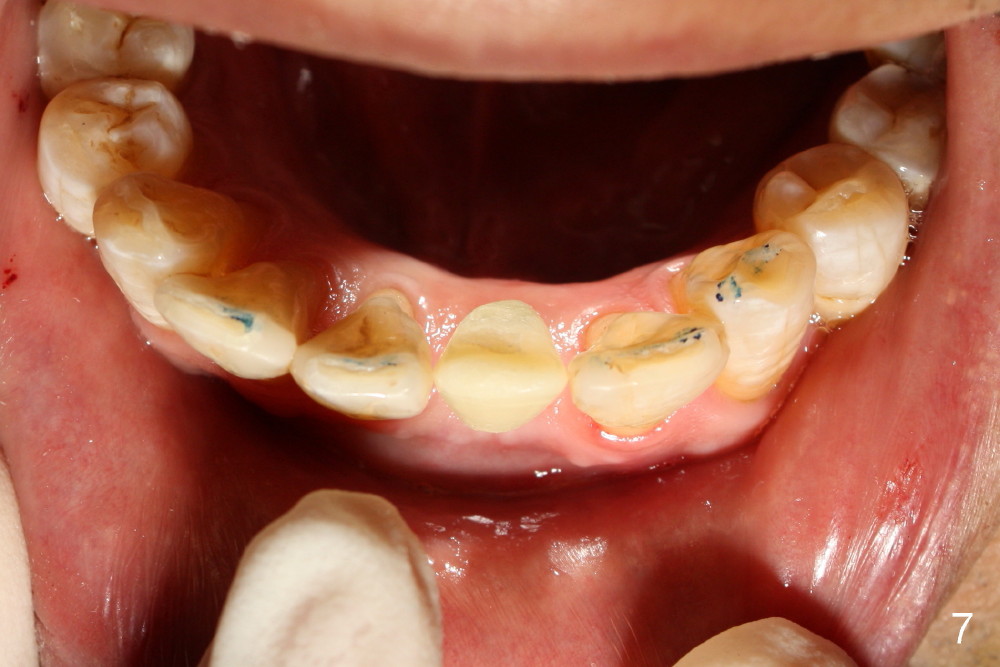

A 3x17 mm one piece implant is planned. Osteotomy is created by a 1.5 mm pilot drill at the depth of 14 mm without incision (Fig.2); it is close to a neighboring incisor. The trajectory of the osteotomy is intended to be changed (Fig.3 red) without success (white, 17 mm deep). With measurement and calculation, the 3x17 mm implant is not expected to touch the root of the adjoining tooth. In fact it is fine with insertion torque between 50-60 Ncm (Fig.4). Without incision, the papillae appear to form immediately following implantation (Fig.5). With adjustment of the abutment (Fig.6), an immediate provisional is fabricated (Fig.7).

Fig.10,11 show 7 day follow up. The permanent crown is seated 4.5 months postop (Fig.12). Minimal bone resorption occurs at the crest 4 months postop (Fig.13), which is most likely associated with conservative approach (flapless). The patient returns for follow up 2.5 months post cementation (Fig.14,15). The implant remains in the bone 4 years post cementation (Fig.16 CT coronal section; lingual thread exposure, corresponding to preop defect in Fig.1). There is mild coronal bone resorption 5 years 4 months post cementation (Fig.17).